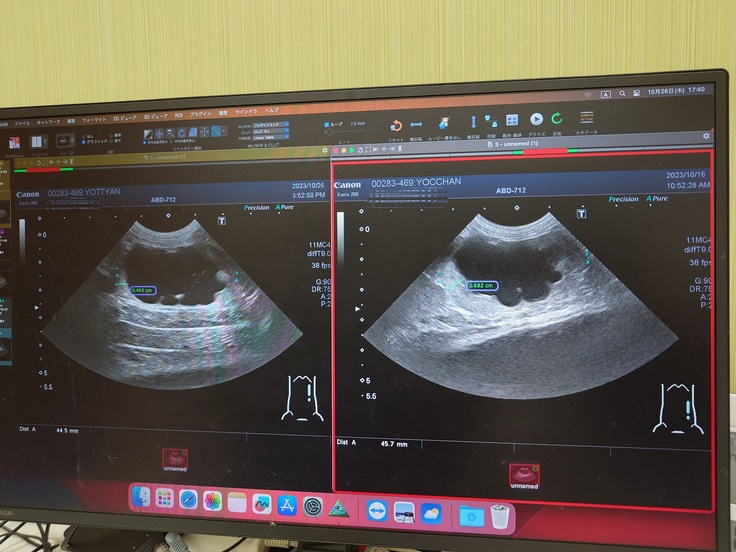

●左側の腎臓と腎盂が肥大して、ほとんど機能していない状態。(右側の腎臓と腎盂は正常)

●11月25日(土)抜糸とエコー検査

退院してからエコー検査をしたところ、手術後に本来なら腎臓の腎盂の大きさが小さくならないといけないけど腎盂の大きさが変わってないので(おしっこが溜まったままになっている)、術後に尿管にカテーテルを入れているので、尿管がカテーテルの太さに広がったまま、まだ元の細さに戻りきっていないことや、ほとんどない症例だけど尿管が太いまま戻っていないから膀胱から腎臓に逆流していることが考えられるので、尿の健康を維持するサプリを1日2回飲み続けてもらうことと、2か月に1回通院して検査をして経過観察をさせてほしいという話になりました。今後はサプリはかかりつけの病院で処方してもらって、検査や経過観察は専門の病院に通うことになりました。